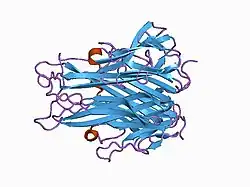

The secreted extracellular portion, denoted sTNF, consists of 157 amino acids.[22] Unlike tmTNF, sTNF can only bind to TNFR1.[10] The secondary structure of sTNF consists primarily of alternating strands that join into two sheets, known as antiparallel β-sheets. The two sheets are layered on top of each other, forming a wedge shape known as an antiparallel β-sandwich. Remarkably, this structure is similar to those seen on the coats of viruses. The last 9 residues of the C-terminus are locked into the middle strand of the bottom sheet, and are necessary for bioactivity.[22]

Both tmTNF and sTNF are only bioactive as homotrimers, whereas individual monomers are inactive.[10] The rate at which TNF trimers disassemble is constant, whereas the rate at which TNF trimers assemble increases with TNF concentration. This causes TNF to be mostly trimers at high concentrations, whereas TNF is mostly monomers and dimers at low concentrations.[23] The coexistence of TNF dimers and trimers in dynamic equilibrium suggests that TNF might be a morpheein.[24] Small molecules that stabilize TNF dimers and prevent the assembly of TNF trimers present a potential mechanism for inhibiting TNF.[25]